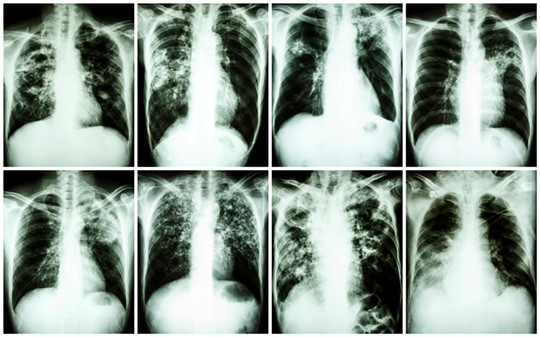

Illustrasjonsfoto: Thinkstock

I en kohort på over 500 000 mennesker som innvandret til England, Wales og Nord-Irland i perioden 2006 – 12, er forekomst av tuberkulose og risikofaktorer for utvikling av sykdommen etter ankomst undersøkt (1). Alle studiedeltakerne var fra land med høy tuberkuloseforekomst, og de var undersøkt med røntgen av lungene før avreise fra hjemlandet. Ved røntgenfunn som tydet på tuberkulose, ble det tatt dyrkningsprøver, som måtte være negative før innreisetillatelse ble gitt.

Etter 2,45 år gjennomsnittlig oppfølging ble det påvist tuberkulose hos 1 873, tilsvarende en insidens på 147 tilfeller per 100 000 personår (95 % KI 140 – 154). I en tilleggsanalyse var det kun 35 av rundt 300 000 deltakere som hadde smittet andre etter at de hadde innvandret. De som hadde funn forenlig med aktiv tuberkulose på røntgenbildene, men negativ dyrkningsprøve ved screening før innreise, hadde om lag tre ganger så høy risiko for å få påvist sykdommen i løpet av de neste årene sammenlignet med dem som hadde normale funn. Risikoen var også større jo høyere forekomsten av tuberkulose var i deltakerens opprinnelsesland.